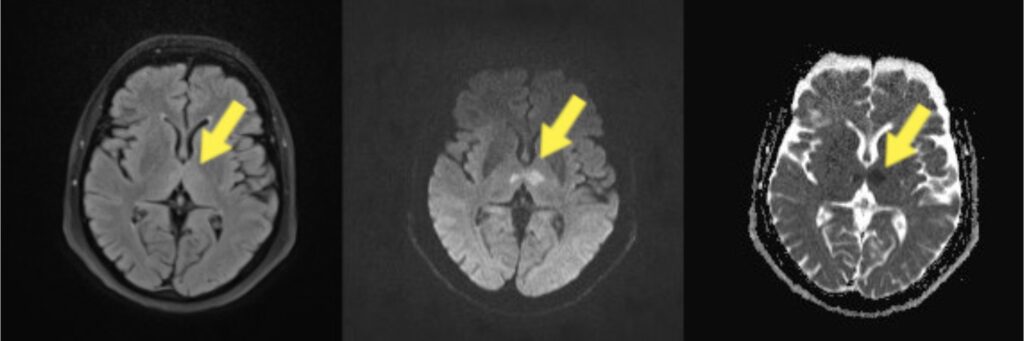

Po prijamu u OHBP bolesnica je disala spontano, suficijentno, bila je izrazito hipertenzivna (vrijednosti krvnoga tlaka 230/110 m mHg) uz uredan elektrokardiografski (EKG) zapis, uredne vrijednosti glukoze i tjelesne temperature te uredan somatski status. U neurološkom statusu bila je prisutna somnolencija bez odgovarajućeg verbalnog odgovora, uz otvaranje oči na poziv. Zjenice su bile uže, izokorične, simetrične i fotoreaktivne uz urednu bulbomotoriku i negativne meningealne znakove. Asimetriju lica nije imala, ali je perzistirala desnostrana slabost po centralnom tipu. Radi kliničke slike cerebrovaskularnog inzulta bio je pokrenut protokol za neurointervenciju. Rezultati učinjenih pretraga, kompjuterizirane tomografije (engl. computed tomography, CT) mozga, CT angiografije karotidnih, vertebralnih i intrakranijskih krvnih žila nisu pokazali znakova svježe hemoragije i ishemije, kao ni vidljivog ispada perfuzije. U tijeku radiološke obrade u bolesnice je došlo do normalizacije krvnog tlaka i regresije desnostrane slabosti, ali bez potpunog oporavka stanja svijesti i uspostave verbalnog kontakta. Po prispijeću urednih nalaza učinjene neuroradiološke obrade, a u nedostatku fokalnog neurološkog ispada proširila se obrada u svrhu pronalaska druge etiologije poremećaja stanja svijesti. Proširena laboratorijska obrada pristigla je uredna, izuzev pozitivnog nalaza benzodiazepina u urinu koje je bolesnica imala u kroničnoj terapiji. Primjena flumazenila intravenski bila je bez kliničkog odgovora. U daljnjem tijeku zbog razvoja izrazite mioze zjenica obostrano bez oporavka budnosti postavljena je sumnja na leziju moždanog debla, što je bio ključan trenutak kliničke prezentacije. Indicirana je hitna magnetska rezonancija (MR) mozga u dogovoru s dežurnom radiološkom službom kojom se dokazala akutna ishemijska lezija u irigacijskom području arterije Percheron (obostrano talamično i rostralno mezencefalično) (slika 1).

Slika 1. Radiološke snimke bolesnice. Na lijevoj slici prikazana je FLAIR sekvenca (engl. Fluid-Attenuated Inversion Recovery), na kojoj se uočava diskretna zona povišenog signala. Na istom mjestu, na DWI/ADC sekvencama (engl. Diffusion Weighted Imaging / Apparent Diffusion Coefficient), prikazanim na srednjoj i desnoj slici, vidi se restrikcija difuzije.